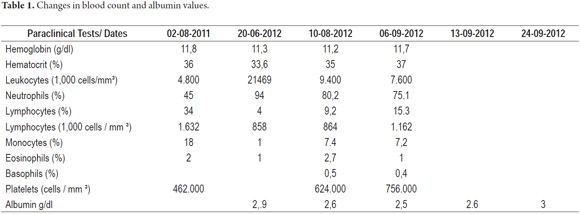

Physical examination: the patient was clinically stable with jaundiced skin and conjunctiva. Patient experienced pain on deep palpation of the left upper abdominal quadrant. A complete blood count and a liver profile reported the listed in Table 1.

Given that clinical and paraclinical examinations indicated extrahepatic cholestasis, it was decided to perform ERCP. A posteroanterior chest x-ray during preoperative cardiovascular assessment showed dextrocardia (Figure 1).